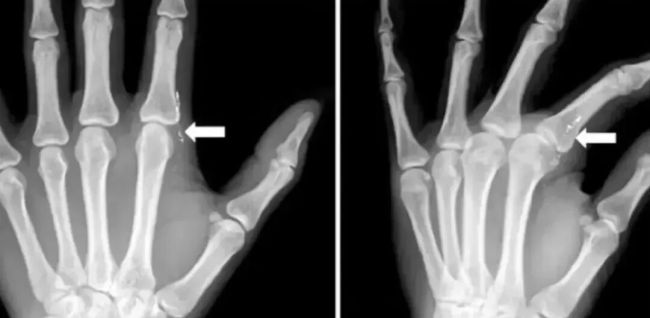

J Hand Surg Asian Pac 曾发表过这样一个病例[1]:一名 42 岁的妈妈去看病,觉得「左食指有异物感」。

医生追问病史了解到,她在 1 个月前在给女儿量体温时,不小心打碎水银温度计。清理体温计碎片的时候,左手指被刺伤,当时觉得没有大碍,就没有就诊。

医生发现,患者左手手指有肉芽组织,检验血液、尿液后发现,有汞中毒的迹象。

左食指第二掌趾关节桡侧疼痛

X 片可见皮下线状高密度影